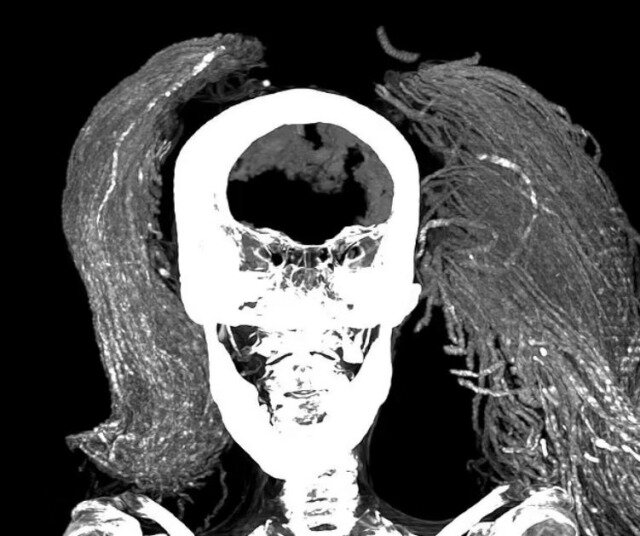

Sonxeber.az xarici mənbəyə istinadən xəbər verir ki, "Qışqıran qadın" adlandırılan bu mumiya ölüm anında ağrıdan qışqırarkən donub qalmış kimi görünür. 1935-ci ildə aşkar edilən mumiya qara parik və qiymətli üzüklər taxan qadına məxsusdur.

Alimlər ən son texnologiyalardan istifadə edərək mumiyanı tədqiq ediblər. Araşdırmalar göstərib ki, qadın təxminən 48 yaşında, boyu 1,54 metr olub və yüngül onurğa artritindən əziyyət çəkirmiş.

Mumiyalama prosesində bahalı materiallardan istifadə edilib ki, bu da qadının əhəmiyyətli bir insan ola biləcəyini göstərir. Həkimlər qadının üzündə "kadavra spazmı" ola biləcəyini deyib. Bütün bunlar şiddətli və ağrılı bir ölümü göstərir.

Maraqlıdır ki, o dövrün mumiyalama ənənəsinin əksinə olaraq qadının daxili orqanları çıxarılmayıb. Bu, mumiyanın bu vəziyyətdə qalması ilə bağlı yeni suallar doğurur. "Frontiers in Medicine" jurnalında dərc olunan bu araşdırma qədim Misirdə həyat və ölüm haqqında yeni məlumatlar təqdim edir. "Qışqıran qadın"ın ölüm səbəbi hələ də sirr olaraq qalır.